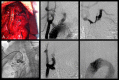

Introduction: The management of thoracic aortic disease involving the ascending aorta, aortic arch and descending thoracic aorta are technically challenging and is an area in constant development and innovation.

Results: A total of 95 patients treated for thoracic aortic diseases in this period, 18 underwent hybrid treatment and entered in this study. The average ages were 62.3 years. The male was present in 66.7%. The technical and therapeutic success was 94.5% e 83.3%. The perioperative mortality rate of 11.1%. There is any death during one-year follow- up. The reoperation rates were 16.6% due 2 cases of endoleak Ia and one case of endoleak II. There is any occlusion of anatomic or extra anatomic bypass during follow up.

Conclusion: In our study, the hybrid treatment of aortic arch disease proved to be a feasible alternative of conventional surgery. The therapeutic success rates and re- interventions obtained demonstrate the necessity of thorough clinical follow-up of these patients in a long time.